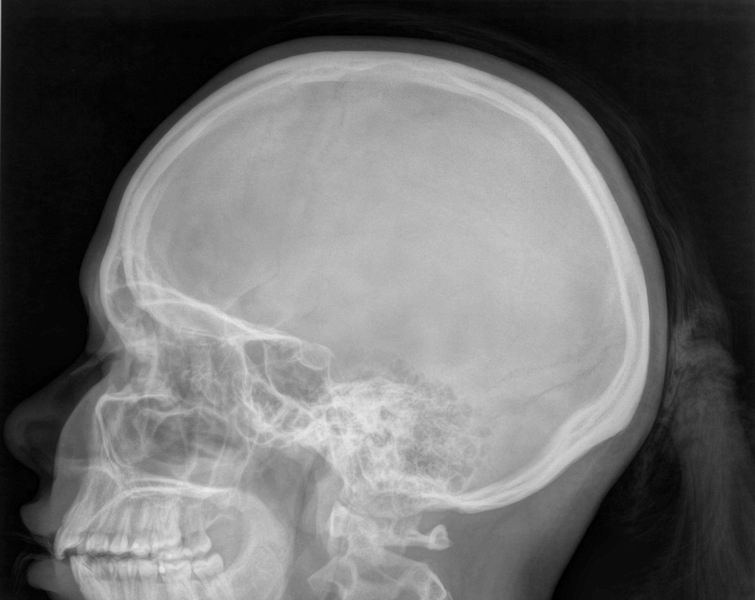

Schedel